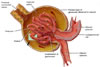

| Glomerulus |

Glomerulus |

Glomerulus |

Glomerulus |

| 1-Küçük kan damarları ya da sinir liflerinin kümesidir. Özellikle bir böbrek tüpçüğünün proksimal ucundaki kapiller yumağıdır. 2-Böbrekteki nefronların bowman kapsülü içinde bulunan kılcal kan damarları ağıdır. Örnek: Glomerulusa gelen kanin icinde büyük maddeler (kan proteinleri vs.) süzülür ama daha küçük olan glikoz vb. maddeler yollarina devam ederler. |